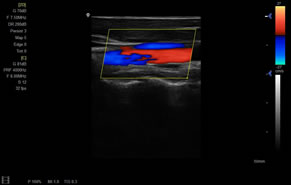

> 彩色血流量圖(CDE)

> 彩色血流分辨增強技術(shù)

廣泛適用于腹部、婦產(chǎn)科、心臟、小器官、乳腺、肌骨及外周血管等諸多方面的診查,讓您在臨床超聲診斷應(yīng)用領(lǐng)域得心應(yīng)手,綻放異彩。